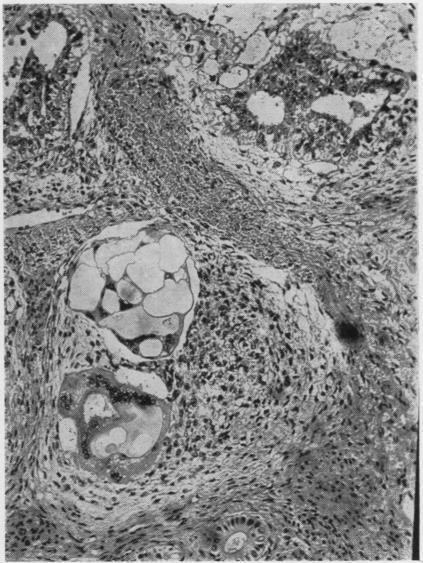

Developmental stages of embryo-like bodies in teratoma testis.